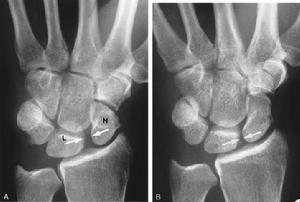

月骨脫位--檢查(1)X線正位片:可見腕骨排列紊亂,頭狀骨與月骨影重疊,舟月間隙增大,舟骨長軸變短,呈皮質環征或舟骨鏇轉,月骨脫位失去四邊形結構,呈三角形影。

(2)X線側位片:出現月骨周圍背側脫位,第3掌骨、頭狀骨與月骨、橈骨失去正常共軸線關係,第3掌骨及頭狀骨的軸線位於月骨及橈骨軸線背側,在此基礎上當月骨向掌側傾斜時,提示為動態性月骨周圍背側脫位,月骨掌側脫位時可見第3掌骨、頭狀骨、橈骨共軸承關係不變,而月骨位於以上諸骨軸線掌側。

月骨脫位X線正位片可見月骨輪廓,由梯形變為三角形。周圍關節間隙不平行或寬窄不等,側位見月骨掌側脫位輕者,月骨仍位於橈骨遠端凹面內,掌屈過度,橈月關節背側間隙變寬,頭狀骨與月骨背側面相對重者,月骨掌屈大於90°進入腕管內與橈骨遠端、頭狀骨完全分離。月骨周圍脫位與月骨脫位X線片影像雖然顯著,但漏診率至今仍居高不下。恐怕與X線側位片骨影相互重疊,單一腕骨輪廓難於分辨有關。診斷困難者可做CT檢查。

根據X線片檢查不僅可以明確診斷,尚可對脫位類型進行分類。正常時腕關節正位片上月骨呈四方形,位於橈骨與頭狀骨之間,在側位片上頭骨、月骨、橈骨三者呈直線關係排列,上述關係的異常很易在X線上發覺,因此診斷並不困難。